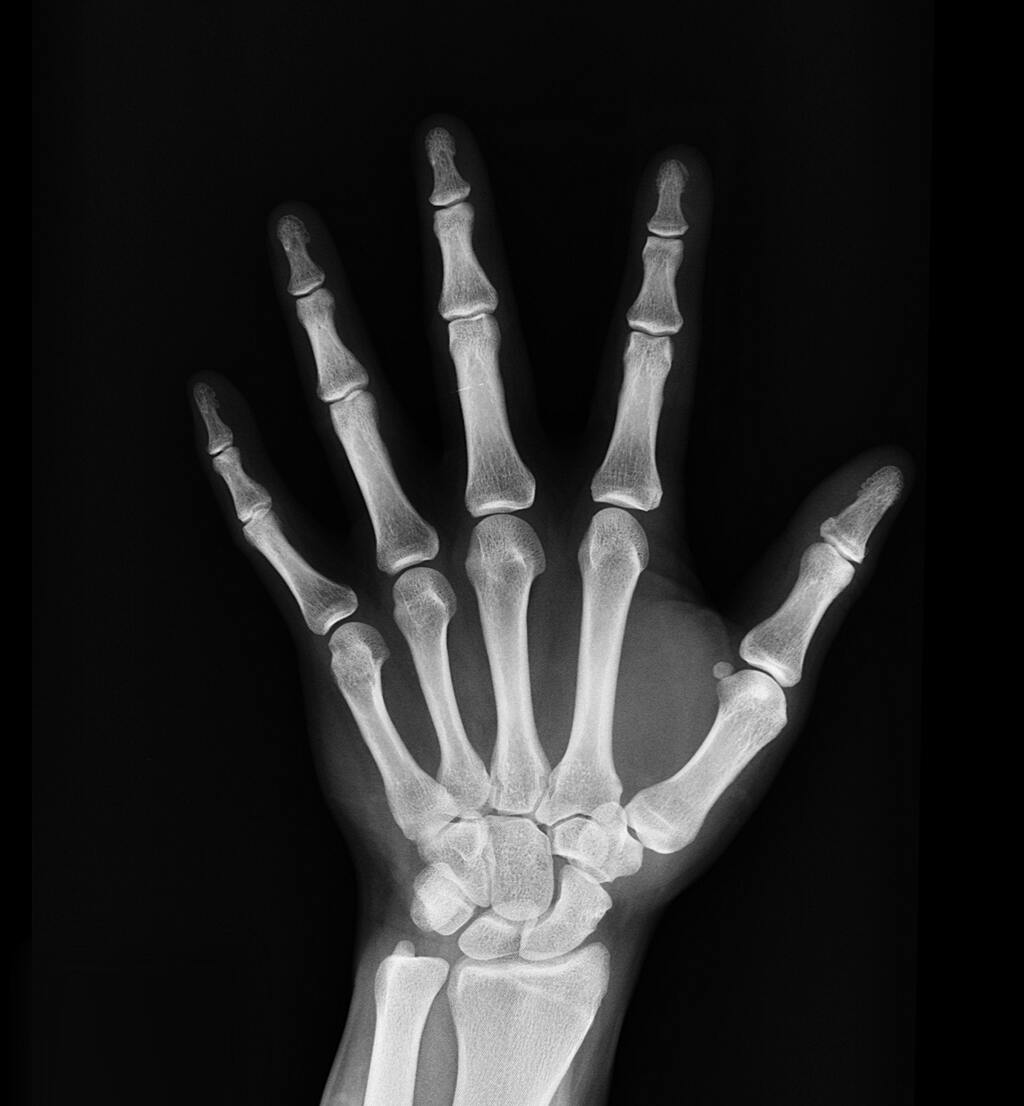

Our Orthopedics and Trauma department offers comprehensive care for injuries and conditions related to the musculoskeletal system. Our expert team utilizes advanced techniques to diagnose and treat fractures, joint issues, and trauma-related injuries.